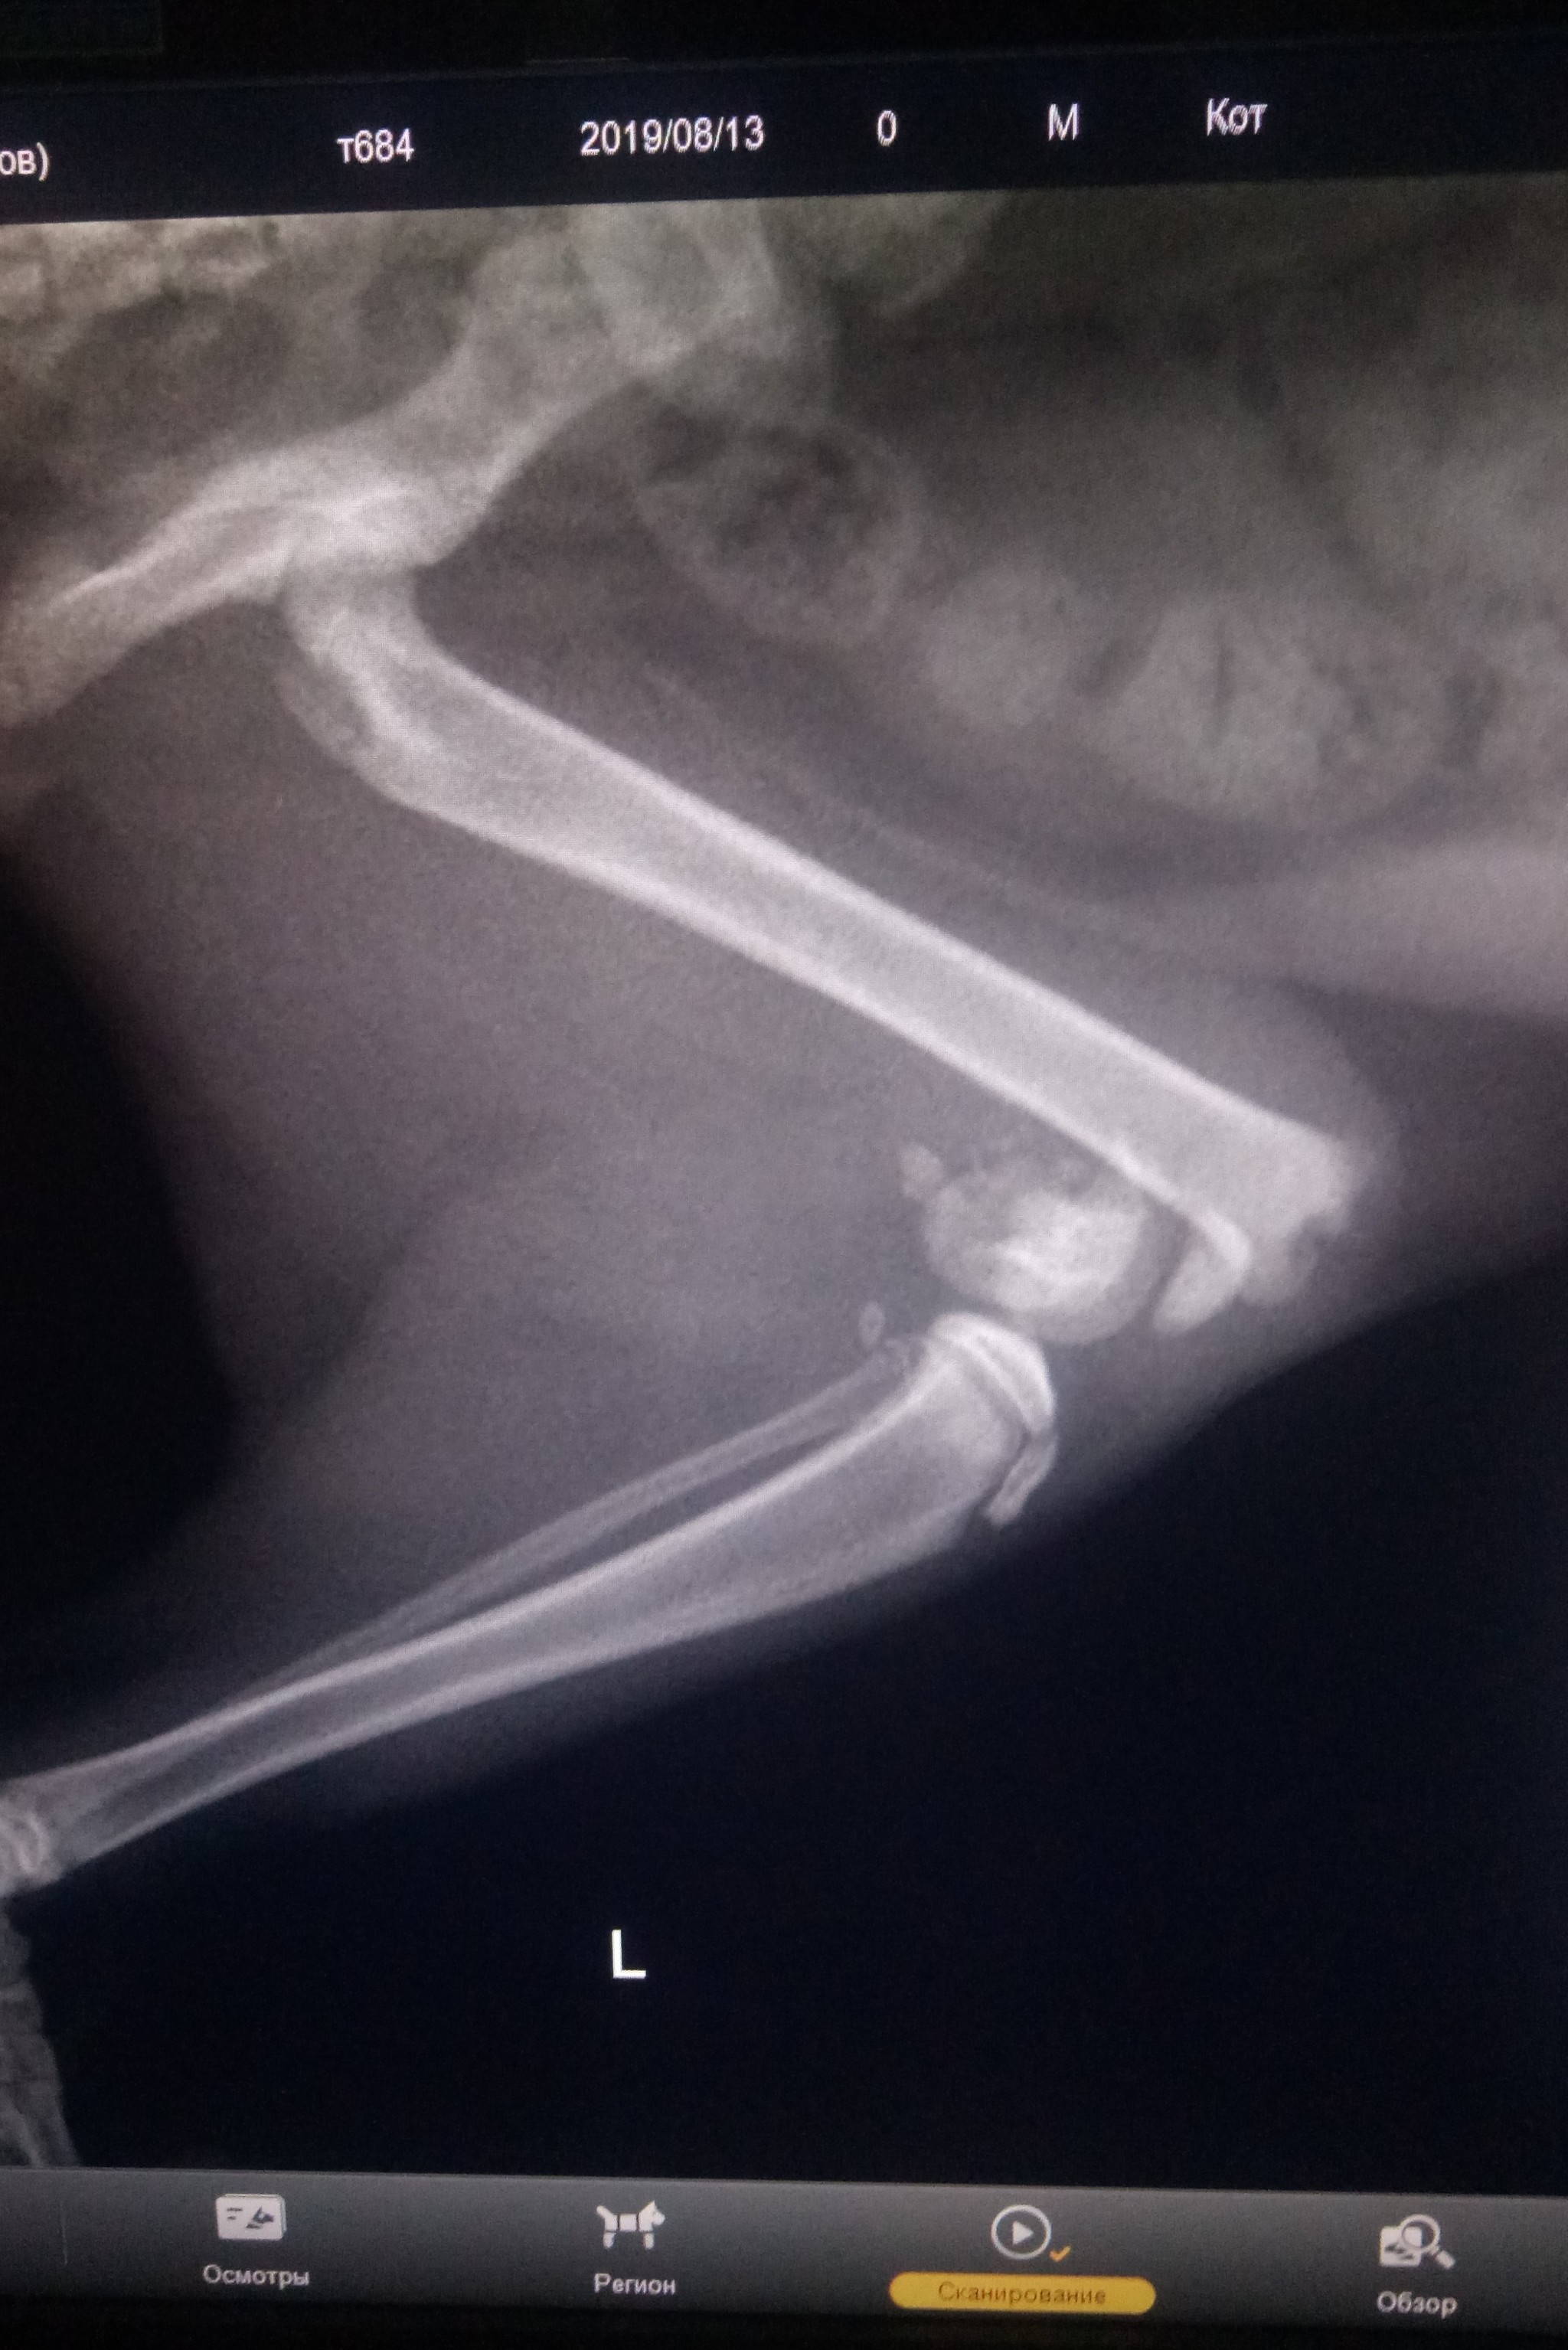

Вот как-то так выглядит кот напросвет. Теплоты там особо не видно, зато есть целый комплект косточек и перелом четвертой пястной кости.

Пока люди отвернулись, Линукс порвал сетку, вышел погулять на карниз и превратился в ракету класса "окно-асфальт". Жив, цел, орёл, месяц ходил со спицей в лапе, и всё равно умудрялся буянить по ночам.